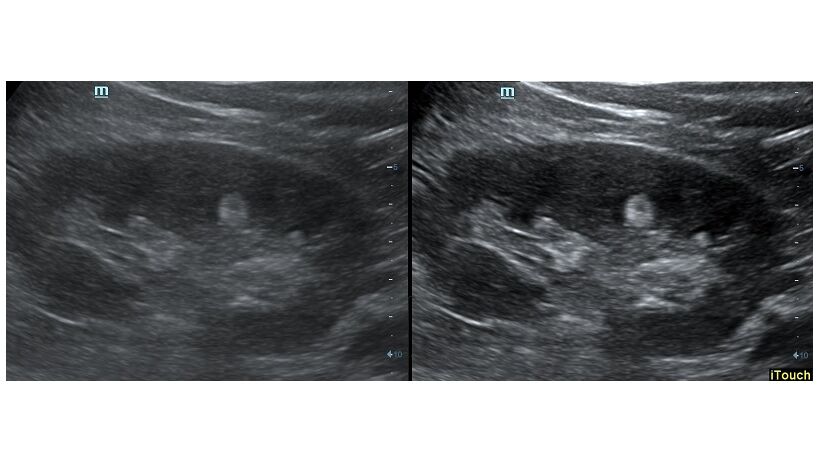

Оптимизация изображения происходит и за счет постобработки. Наиболее часто используемый инструмент - общее усиление (Gain). Усиление делает изображение «ярче», но чем сильнее усиление, тем меньше различия между структурами. Также используются усиление по времени (TGC) и усиление по длине (LGC), которые позволяют изменять отображение на экране послойно, позволяя подсветить гипоэхогенные участки, или, наоборот, снизить визуально эхогенность слишком ярких моментов. Данный вид оптимизации требует много времени, для упрощения работы доктора на приборах Mindray внедрена система автоматической оптимизации - iTouch.